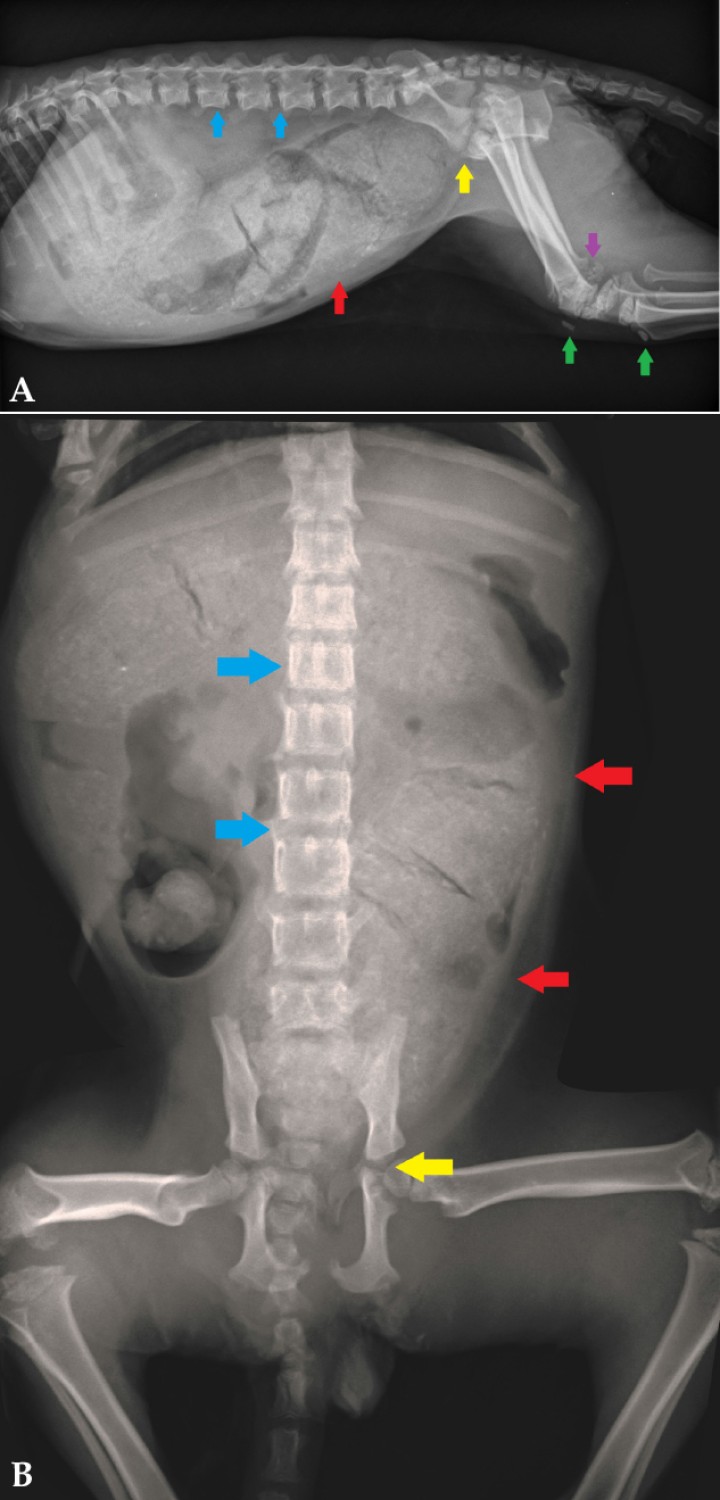

Tras un año de tratamiento, en las radiografías puede observarse el cierre completo de la pelvis, los cuerpos vertebrales de una longitud normal y las líneas de crecimiento de los huesos largos cerradas por completo (Fig. 3). Además, los valores de hormonas tiroideas se encuentran dentro de rango (Tabla 2).

<p>Radiografía en proyección lateral del abdomen y extremidades posteriores del paciente de la Figura 1 tras un año de tratamiento con levotiroxina.</p>

Radiografía en proyección lateral del abdomen y extremidades posteriores del paciente de la Figura 1 tras un año de tratamiento con levotiroxina.